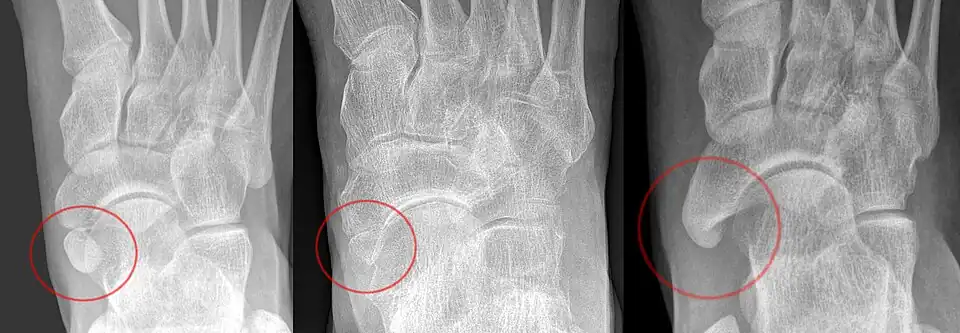

Ankle

Accessory bones at the ankle mainly include:

- Os subtibiale, with a prevalence of approximately 1%.[14] It is a secondary ossification center of the distal tibia that appears during the first year of life, and which in most people fuses with the shaft at approximately 15 years in females and approximately 17 years in males.[14]

- Os subfibulare, with a prevalence of approximately 0.2%.[15]

Os trigonum (further described below) may also be seen on an ankle X-ray.

Foot

| Bone | Prevalence[17] |

|---|---|

| Sesamoid bones | |

| Sesamoids at the metatarsophalangeal (MTP) joint of the great toe | Always present |

| Sesamoid of the second metatarsal | 0.4% |

| Sesamoid of the third metatarsal | 0.2% |

| Sesamoid of the fourth metatarsal | 0.1% |

| Sesamoids of the fifth metatarsal | 4.3% |

| Sesamoid of the interphalangeal (IP) joint of the great toe | 2–13% |

| Ossicles | |

| Os trigonum (not visible in this dorsoplantar projection) | 7–25% |

| Os peroneum | Up to 26% |

| Accessory navicular | 2–21% |

| Os intermetatarseum | 1–13% |

| Os supranaviculare, also called the talonavicular bone | 1.0–3.5% |

| Os calcaneus secundarium | 0.6–7% |

| Os supratalare | 0.2–2.4% |

| Os vesalianum | 0.1–1% |

| Os talotibiale | 0.5% |

Accessory navicular

An accessory navicular bone, also called os tibiale externum, occasionally develops in front of the ankle towards the inside of the foot. This bone may be present in approximately 2–21% of the general population and is usually asymptomatic.[18][19][20] When it is symptomatic, surgery may be necessary.

Os trigonum

The os trigonum or accessory talus represents a failure of fusion of the lateral tubercle of the posterior process of the talus bone. Is estimated to be present in 7–25% of adults.[17] It can be mistaken for an avulsion fracture of lateral tubercle of talus (Shepherd fracture) or a fracture of the Stieda process. In most cases, Os Trigonum will go unnoticed, but with some ankle injuries it can get trapped between the heel and ankle bones which irritates the surrounding structures, leading to Os Trigonum Syndrome.[21]